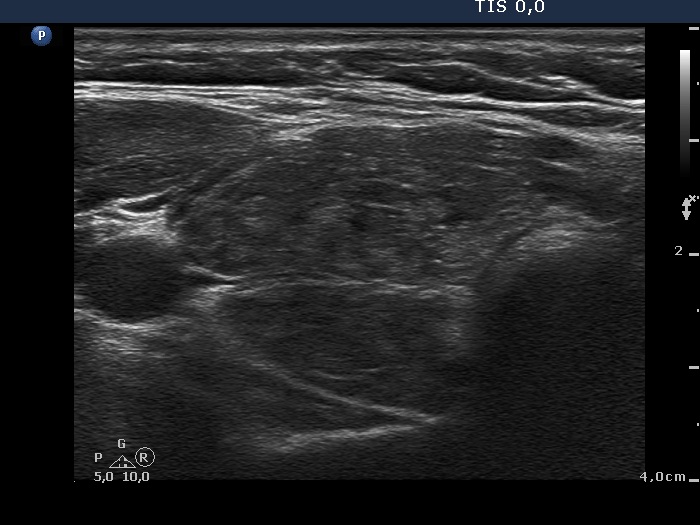

First examination (first row of images):

Clinical presentation: A 39-yr-old woman was referred for evaluation of a newly diagnosed hypothyroidism. She was treated for Graves' hyperthyroidism for 11 and for 7 years. Since than, the thyroid function has been normal.

Palpation: Both lobes were enlarged and nodular on palpation.

Laboratory tests: TSH 10,3 mIU/L, FT4 8.63 pM/L.

Ultrasonography. The thyroid was composed of hypoechoic and isoechoic islets divided by hypoechoic bands. The presentation corresponded to micronodular pattern.Suggestion: daily 75 microgram levothyroxine. The is 3 months, ultrasound in three years.